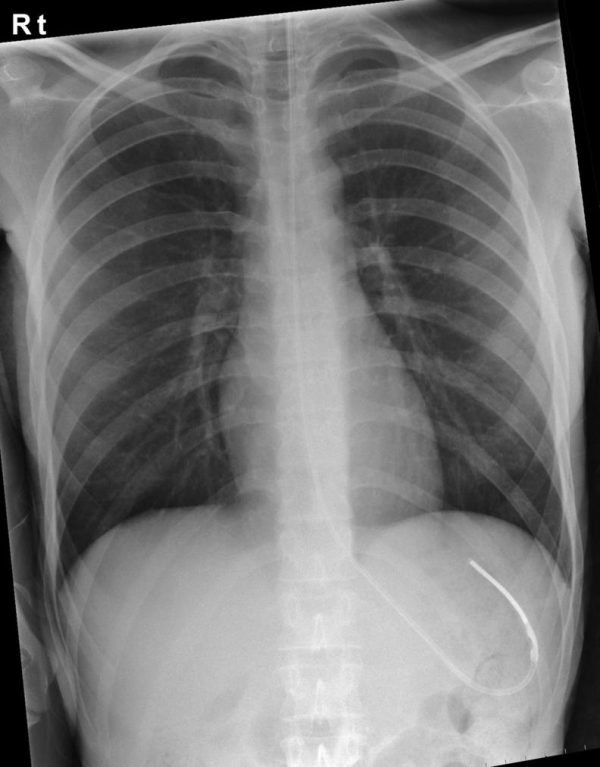

From www.semanticscholar.org

Nasogastric tube insertion in adults who require enteral feeding How Long Do Ng Tubes Last The bottom line is that it's uncomfortable, but it shouldn't be painful, and it may help you avoid more invasive procedures that. How long will my child need a nasogastric tube for? In general, enteral tube feeding is only advised for up to 4 weeks. This appointment may be with one of the dieticians at addenbrooke's or at your local.. How Long Do Ng Tubes Last.

From oxfordmedicaleducation.com

Nasogastric (NG) Tube Placement Oxford Medical Education How Long Do Ng Tubes Last Your nasogastric tube will help you to meet your nutritional needs and administer any medications. How long will my child need a nasogastric tube for? How long will i need the ng tube for? Your dietician will provide a plan. Learn about the indications, contraindications, placement, management, and complications of nasogastric and nasoenteric. Find out how to care for the. How Long Do Ng Tubes Last.